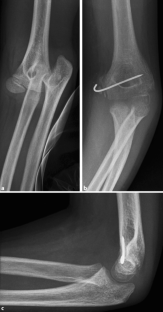

Es wird ein zum Unfallzeitpunkt 10-jähriger Junge mit Ellenbogengelenksluxation und Fraktur des Epicondylus medialis links präsentiert. Im Verlauf nach erfolgter medialer Kirschner-Draht-Osteosynthese wird eine Läsion des N. medianus beschrieben. Dass auch der N. ulnaris geschädigt ist, fällt erst mehr als 3 Jahre postoperativ auf. Daraufhin erfolgt eine operative Dekompression und Neurolyse des N. medianus und ulnaris, und es wird das Ergebnis 3½ Jahre postoperativ präsentiert.

We present the case of a 10-year-old boy with a dislocation of the elbow and fracture of the medial epicondyle. After closed reduction and K‑wire fixation from medial, he presents a median nerve palsy. That a lesion of the ulnar nerve is also present is only noticed 3½ years posttraumatically. A surgical decompression and neurolysis of the ulnar and median nerve is performed and the postoperative grip and key strength presented.

Abb. 2

Abb. 3